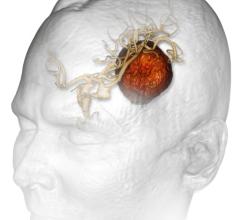

Cancer patients with limited brain metastases (one to four tumors) 50 years old and younger should receive stereotactic radiosurgery (SRS) without whole brain radiation therapy (WBRT), according to a study in the March 15, 2015 issue of the International Journal of Radiation Oncology • Biology • Physics (Red Journal).

Accuray Inc. announced that the first patient treatment has been completed using the CyberKnife M6 System with the InCise Multileaf Collimator (MLC). The treatment was administered as a multidisciplinary effort between Steven Burton, M.D., from the Department of Radiation Oncology, and Johnathan Engh, M.D., from the Department of Neurosurgery at the University of Pittsburgh Medical Center (UPMC) in Pittsburgh, Pennsylvania.